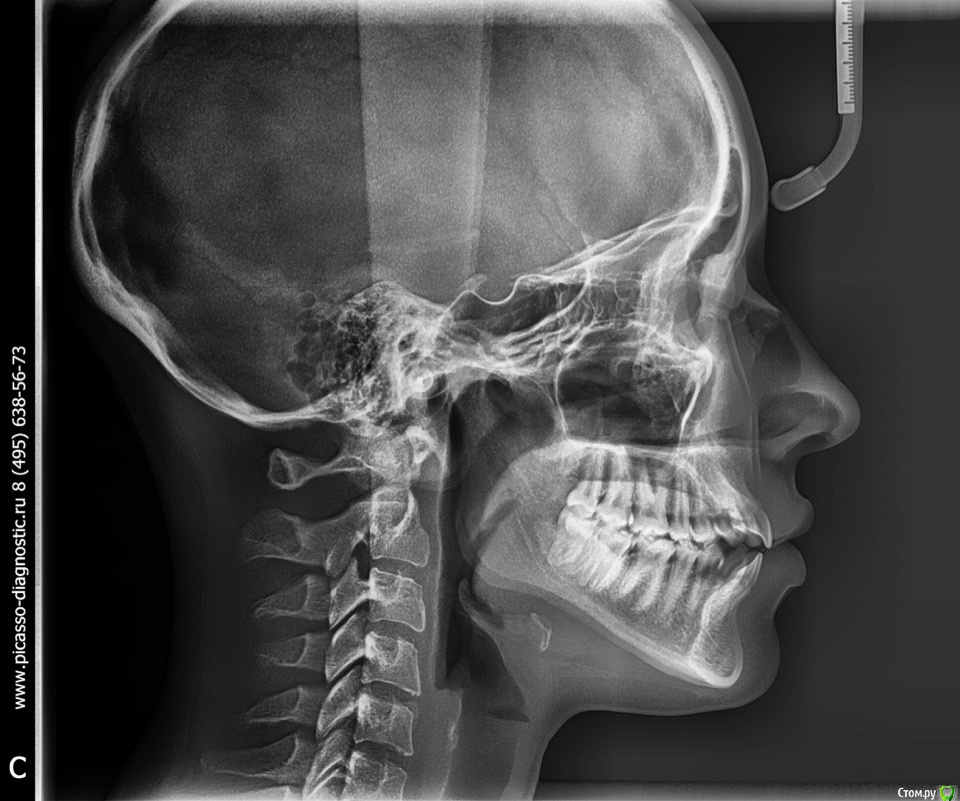

КошкинДом Опубликовано 3 сентября, 2019 Поделиться Опубликовано 3 сентября, 2019 Приветствую всех!Меня зовут Александра, мне 25 лет и я ипохондрик, переживаю в данный момент из-за своих зубов. Возможно кто-то из вас сможет дать мне совет Пол года назад у меня немного заболел левый ВНЧС, было неудобно спасть, затем все прошло и больше ничего не беспокоит до сих пор, только иногда хрустит в левом суставе и легкий дискомфорт в ухе после еды. Я заметила что в течении этих 6 месяцев мой прикус открылся ~2мм Вот мое фото 2017:А вот сейчас: Также прикрепляю два фото, ТРГ и ОПТГ: Мой вопрос: Меня сейчас ничего не беспокоит в моих зубах, можно ли и дальше спокойно жить? Если кто-то сталкивался с подобным дайте совет Всем хорошего дня 1 Ссылка на комментарий

КошкинДом Опубликовано 4 сентября, 2019 Автор Поделиться Опубликовано 4 сентября, 2019 Заключение ТРГ: скелетный 1 класс с выраженной тенденцией к 3 классу. Вертикальная резцовая дизокклюзия зубоальвеолярная форма. Протрузия резцов верхней челюсти. Нейтральный тип роста челюстей с тенденцией к вертикальному.Сужение нижних воздухоносных путей не выявлено. Ссылка на комментарий